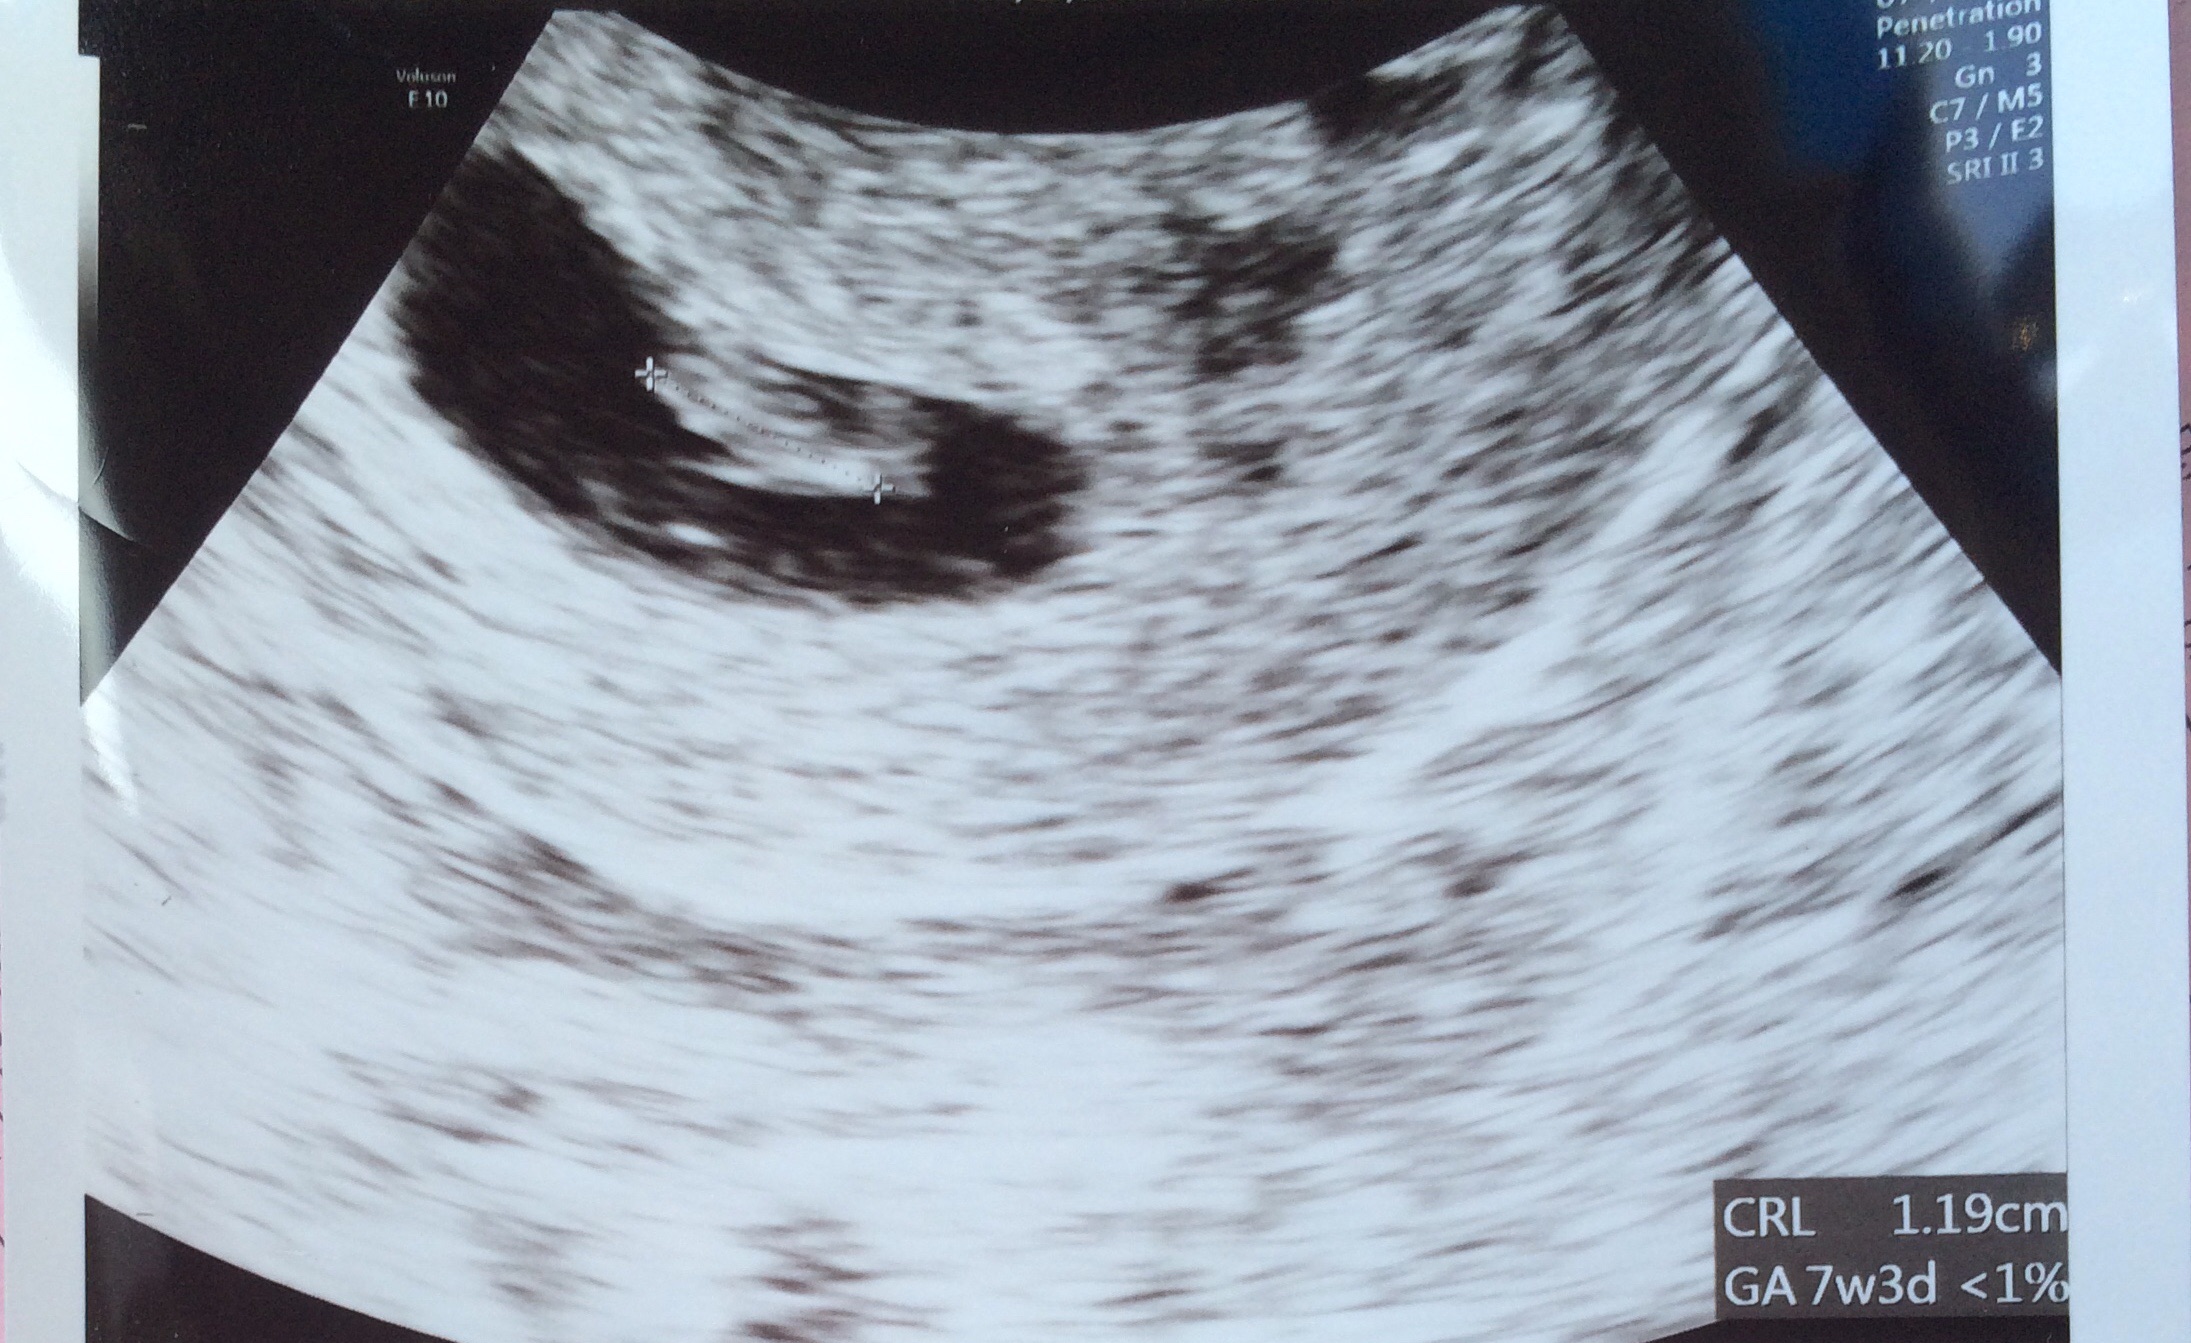

Here is my little one! We are 7 weeks 4 days baby was measuring 7 weeks 1 day and the heartbeat was 128bpm! Best thing ever to see that little heart flicker!